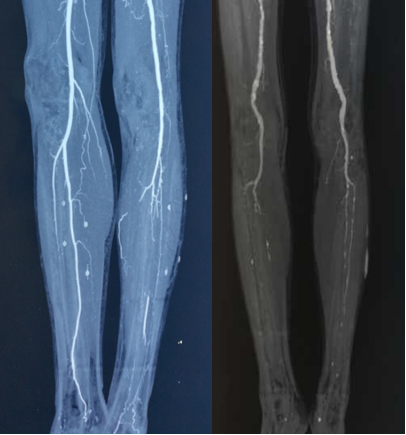

图:下肢动脉硬化闭塞病变CT

图:下肢动脉硬化闭塞病

背景介绍:下肢动脉硬化闭塞病变

下肢动脉硬化闭塞病变的疾病特点:

好发于中老年人群,常表现为多节段闭塞病变。

常合并高血压、糖尿病及肾功能不全等基础疾病。

部分患者就诊时已出现严重肢体缺血(CLI),需及时干预。